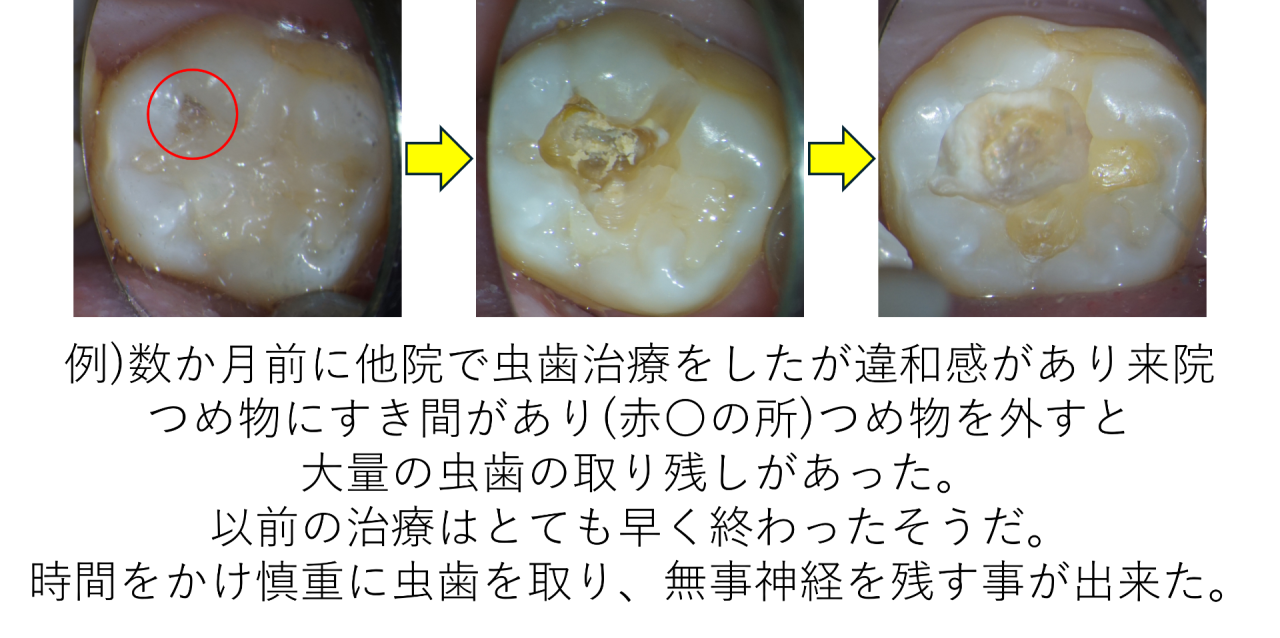

30分しかないのであれば、丁寧な虫歯治療を行うことは難しいため、虫歯の取り残しが起こりやすいです。

最悪の場合、最初から神経を残す事をせずに抜いてしまうことがあります(当院では絶対にしませんが)。

当院では現在虫歯治療は自費のみで行います(1本25,000円)。その理由の一番は【時間】。神経に近い虫歯なら2時間かけることもあります。それだけ虫歯治療は難しく、歯の治療の中で最も大切なことだと思うからです。